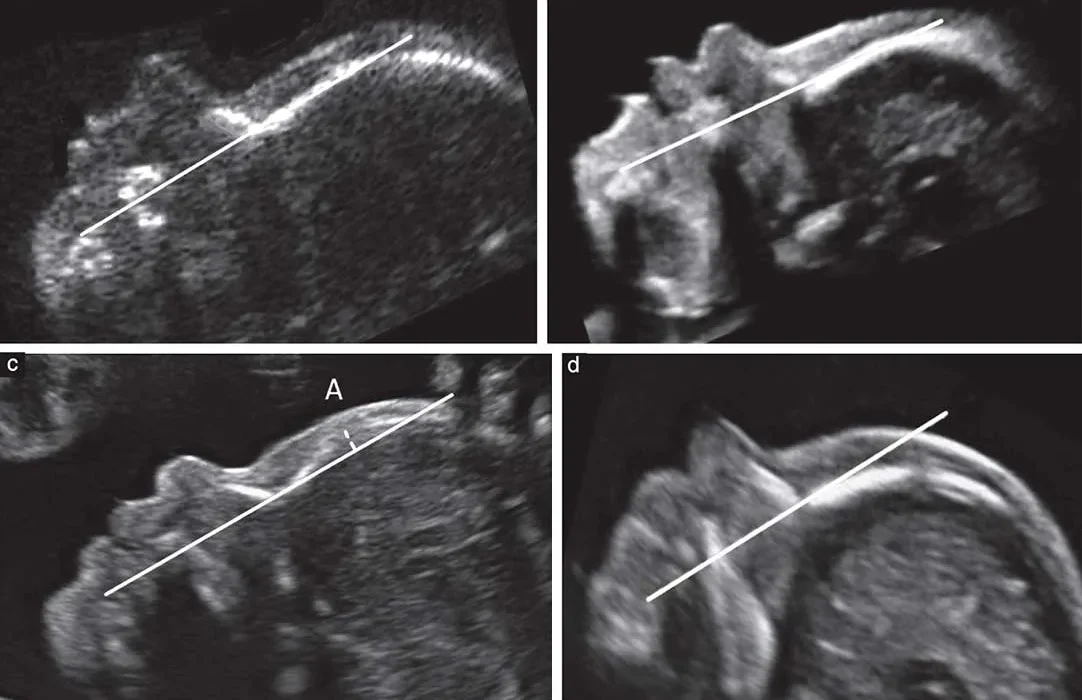

دبیر ستاد ملی جمعیت درباره برخی اظهارات مبنی بر توقف اجرای غربالگری در دوران بارداری، گفت: غربالگری در کشور ما انجام می‌شود و ممنوعیتی برای انجام آن وجود ندارد.

به گزارش کارمیهن، مرضیه وحید دستجردی، در توضیح بیشتر این موضوع اظهار کرد: برخی تلاش داشتند با تصویب قانون، انجام غربالگری را ممنوع کنند؛ اما پیگیری‌ها و اقدامات متخصصان زنان مانع از تحقق این امر شد. در نتیجه، غربالگری همچنان به عنوان یک فرآیند رسمی در نظام سلامت کشور اجرا می‌شود و حتی جایگاه قانونی دارد. از این‌رو، هیچ ممنوعیتی در این زمینه اعمال نشده و برنامه‌های غربالگری همچنان در کشور ادامه دارد.